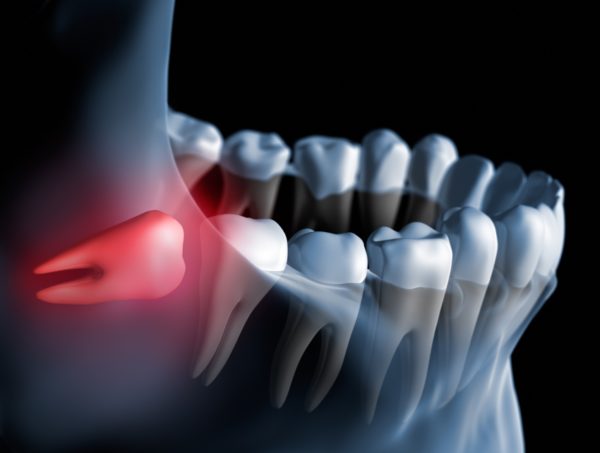

Por que, entre quem ainda tem o siso, muitas vezes vem uma dor e depois some?

A dor é sinal de algum problema. Em geral, ocorre uma inflamação dos tecidos gengivais que circundam os sisos. Se ele estiver semi-incluso, e não nascido totalmente, as inflamações são mais frequentes.

Negligenciar a dor pode ser um problema? Dente do siso principais dúvidas.

Não se pode fazer isso em hipótese alguma. Quando houver sensação dolorosa e inflamação, é preciso procurar o dentista para avaliar a necessidade de remoção do dente ou de limpeza e remoção de bolsa periodontal. Outro procedimento que pode ser feito é uma cirurgia de ulectomia, em que o objetivo é retirar o excesso de gengiva ao redor do siso para facilitar sua higienização diária.